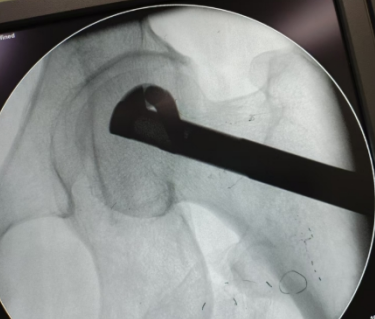

邹国耀主任对王先生的病情进行了详细评估,并组织科室医疗团队开展病例讨论。根据王先生情况,制定了髋关节镜下滑膜清理+髓芯减压死骨刮除后植骨+生物陶瓷棒置入的保髋手术治疗方案:

最终,在邹国耀主任的指导下,陈椿荣副主任医师团队成功为王先生开展了保髋手术治疗。术后经「医生—护士—康复医师」一体化康复,王先生很快出院,下肢功能逐渐恢复。